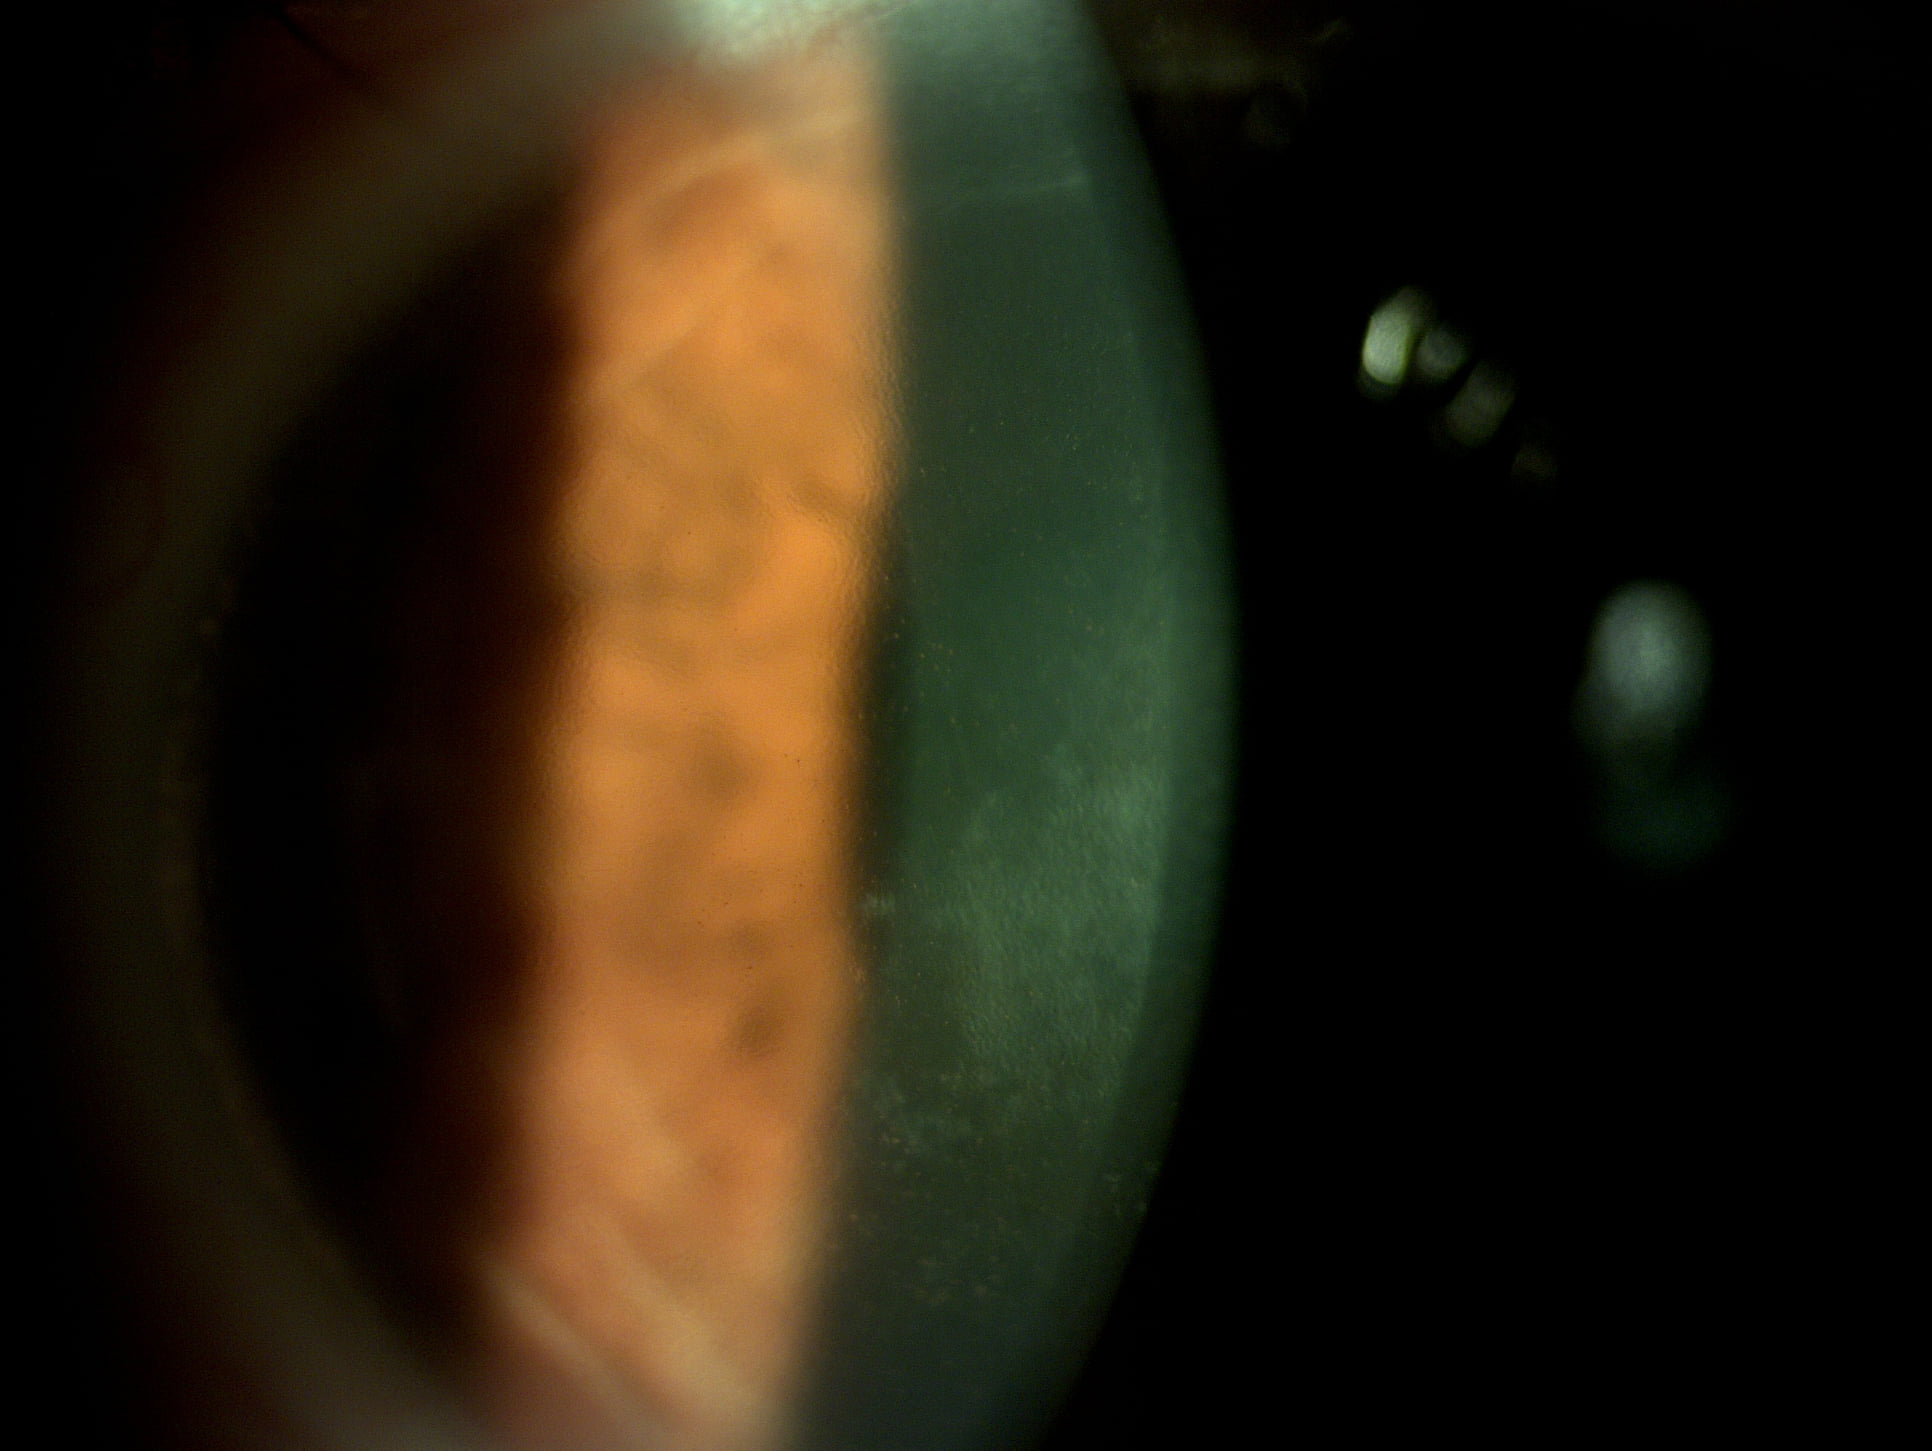

Mai jos, fotografii ale mai multor pacienti de-ai nostri cu Corneea Guttatta în faze medii, sau chiar avansate, la care am efectuat doar operația de cataractă, în urma căreia corneea a „supraviețuit” cu brio și nu a mai fost nevoie – cel puțin până acum – de un trasplant de cornee.